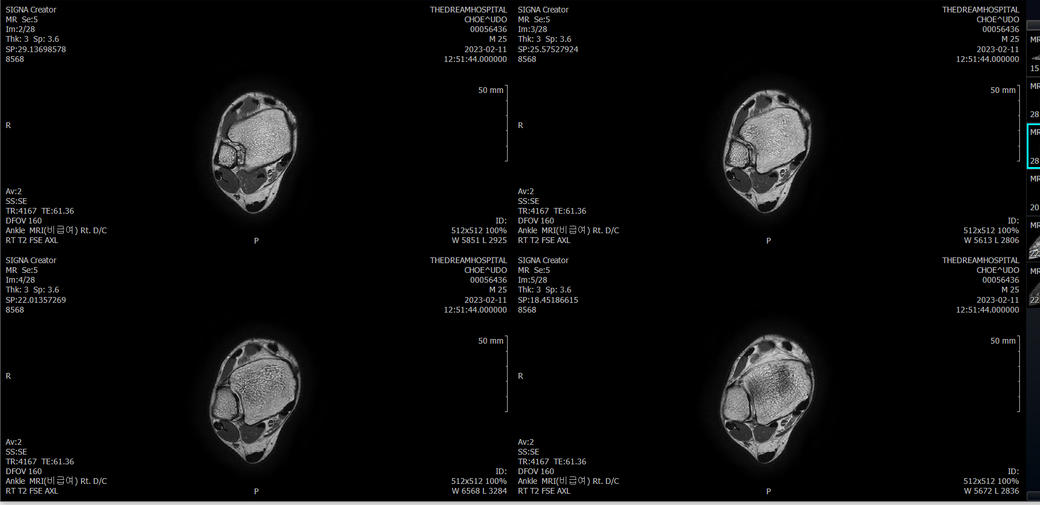

오른발목 mri 전체사진입니다. 제가 병원을 갈수없는상황인지라.... 봐주시면 감사하겠습니다.

엑스레이에서는 문제가 없다고 하여 오른발목 mri촬영했습니다.